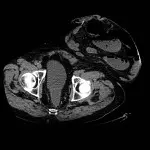

hernia recurrence prevention

Expert Take: No Easy Fixes For Parastomal Hernias